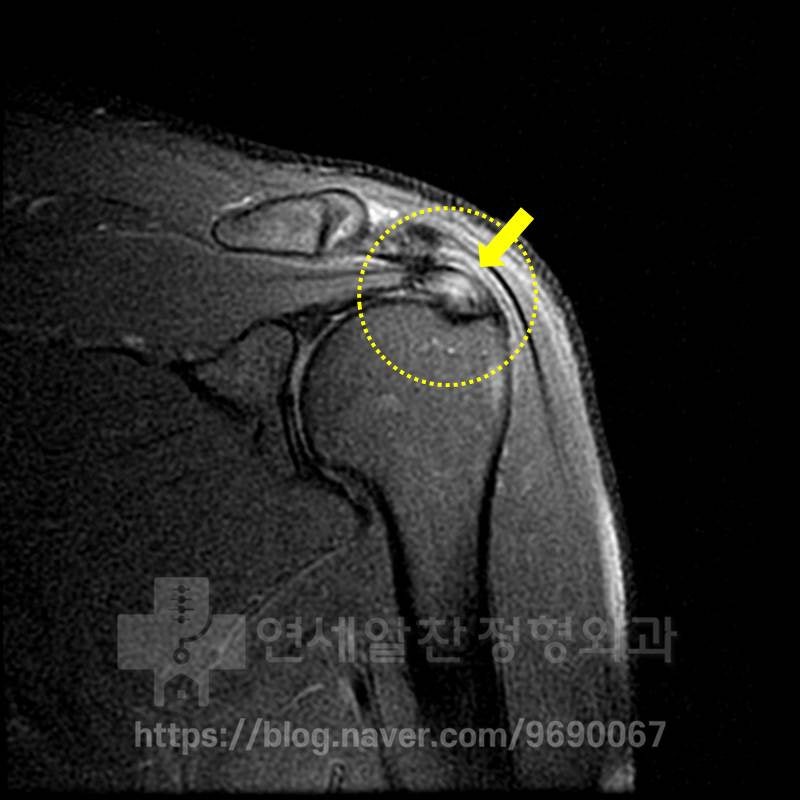

X-ray 상에서는 정상적인 소견이 관찰됩니다.

MRI 상에서 극상근 부위에 정상적으로는 검게 보여야 할 인대가 하얗게 보이면서 심한 염증소견이 보이고 있습니다. 이것을 심한 건증(인대가 약해진것)으로 판단하고 이것에 대한 봉합술을 권고 받은 것으로 보입니다. 하지만 자세히 보면 MRI 상에서 극상근 안에 조그만 까만 점이 보이는 것이 보이며 미세한 석회로 생각됩니다. 그래서 초음파 검사를 통해 다시 한번 확인해 보기로 하였습니다.